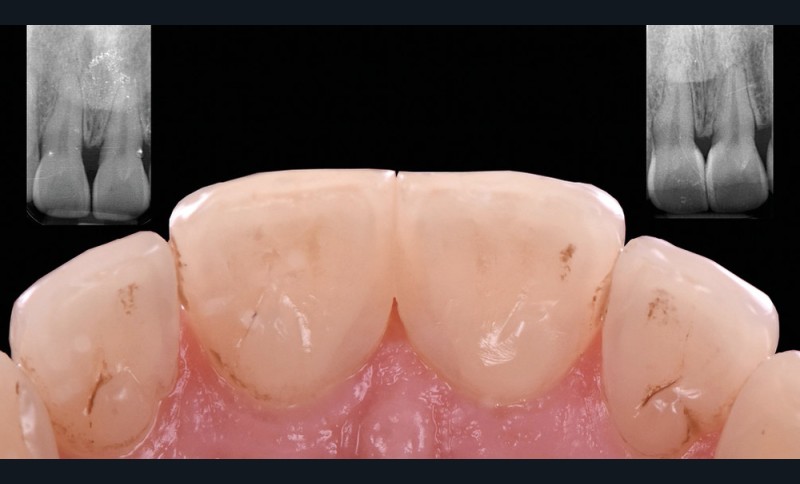

Les triangles noirs

Ils correspondent à une perte de papille interdentaire et sont principalement observés :

– lorsque la distance point de contact/crête osseuse est supérieure à 5 mm ;

– chez des patients présentant une atteinte parodontale avec une perte osseuse associée à une récession horizontale ;

– pour des dents le plus souvent de forme triangulaires ;

– en post-traitement orthodontique.